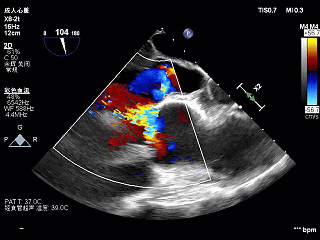

术前超声

超声所见:

主动脉瓣增厚,回声增强,右冠瓣舒张期脱向左室流出道,跨瓣血流线速度加快,峰值压差25mmHg,瓣口探及中重度偏心性反流,反流束冲击二尖瓣前叶及左室侧壁;二尖瓣口探及轻中度反流。

LVEF 46%(反流程度加重,可能导致高估)。

超声诊断:

-

可疑左室壁节段性运动异常

左心系统及右房大

主动脉瓣钙化、右冠瓣脱垂并跨瓣血流速度加快及中重度关闭不全

二尖瓣轻中度关闭不全

升主动脉扩张 主动脉窦扩张

下腔静脉增宽 肺动脉主干增宽 少量心包积液 左室收缩功能减低